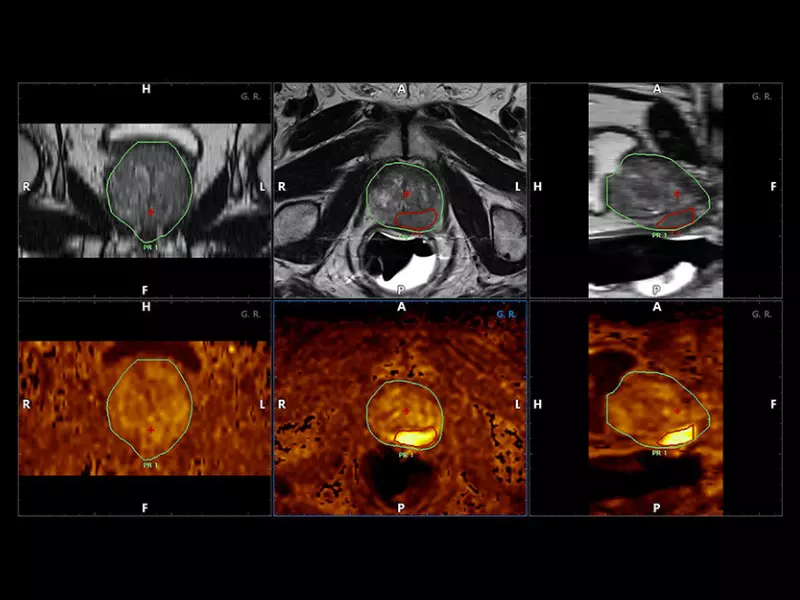

MyLab™X90 - UroFusion Automatic segmentation of the prostate MRI/US, followed by autoregistration of both modalities for targeted biopsies

MyLab™X90 - UroFusion Automatic segmentation of the prostate MRI/US, followed by autoregistration of both modalities for targeted biopsies